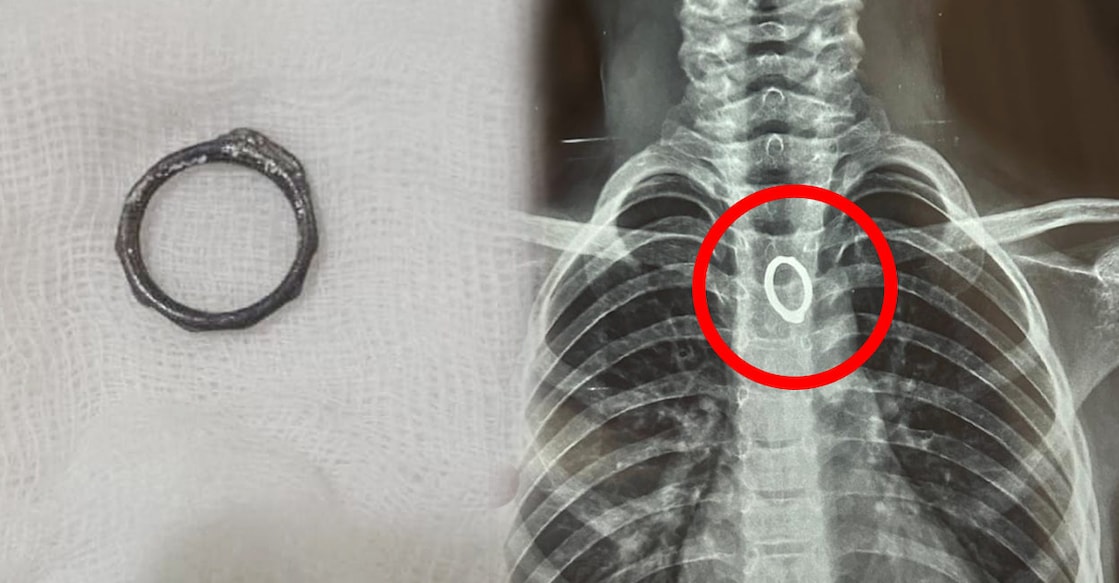

ആലുവ∙ കളിക്കുന്നതിനിടെ ഏഴ് വയസ്സുകാരൻ അബദ്ധത്തിൽ വിഴുങ്ങിയ മോതിരം ഡോക്ടർമാർ സുരക്ഷിതമായി പുറത്തെടുത്തു. ആലുവ കുട്ടമശ്ശേരി സ്വദേശിയായ ബാലന്റെ അന്നനാളത്തിൽ കുടുങ്ങിയ മോതിരമാണ് രാജഗിരി ആശുപത്രിയിലെ ഡോക്ടർമാർ എൻഡോസ്കോപ്പി വഴി പുറത്തെടുത്തത്. കുട്ടി മോതിരം വിഴുങ്ങിയ ഉടൻ തന്നെ വീട്ടുകാർ കുട്ടമശ്ശേരിയിലെ സ്വകാര്യ ആശുപത്രിയിൽ പ്രവേശിപ്പിച്ചു. എക്സറേ പരിശോധനയിൽ മോതിരം അന്നനാളത്തിൽ കുടുങ്ങിയതായി കണ്ടെത്തി. തുടർന്നാണ് എൻഡോസ്കോപ്പി സൗകര്യമുളള രാജഗിരി ആശുപത്രിയിലേക്ക് കുട്ടിയെ മാറ്റിയത്. ഗ്യാസ്ട്രോഎൻട്രോളജി വിഭാഗത്തിലെ വിദഗ്ധരായ ഡോക്ടർമാരുടെ നേതൃത്വത്തിൽ എൻഡോസ്കോപ്പ് ഉപയോഗിച്ച് മോതിരം സുരക്ഷിതമായി പുറത്തെടുത്തു. ഗ്യാസ്ട്രോ എൻട്രോളജിയിലെ ഡോ. തരുൺ ടോം ഉമ്മൻ, ഡോ. ജോമോൻ എം. ജോർജ്, ഡോ. ജിതിൻ ജോൺ, ഇന്റർവെൻഷണൽ ഹെപ്പറ്റോബിലിയറി റേഡിയോളജി വിഭാഗത്തിലെ ഡോ. എസ്. രാജേഷ്, ഡോ. അഖിൽ ബേബി എന്നിവർ ചികിത്സയ്ക്ക് നേതൃത്വം നൽകി. ആരോഗ്യനില തൃപ്തികരമായതോടെ, കുട്ടിയെ ഡിസ്ചാർജ് ചെയ്തു. കുട്ടികൾ അബദ്ധത്തിൽ വസ്തുക്കൾ വിഴുങ്ങുന്ന സാഹചര്യങ്ങളിൽ അതിവേഗം വിദഗ്ധ ചികിത്സ ലഭ്യമാക്കുന്നത് അപകടസാധ്യത കുറയ്ക്കുമെന്ന് ഡോക്ടർമാർ ഓർമിപ്പിച്ചു. അന്നനാളത്തിലോ ശ്വാസനാളത്തിലോ ഇത്തരം വസ്തുക്കൾ കുടുങ്ങുന്നത് ഗുരുതരമായ ആരോഗ്യപ്രശ്നങ്ങൾക്ക് കാരണമാകുമെന്നതിനാൽ അടിയന്തര വൈദ്യസഹായം തേടണമെന്ന് ഡോ. ജോമോൻ എം. ജോർജ് പറഞ്ഞു